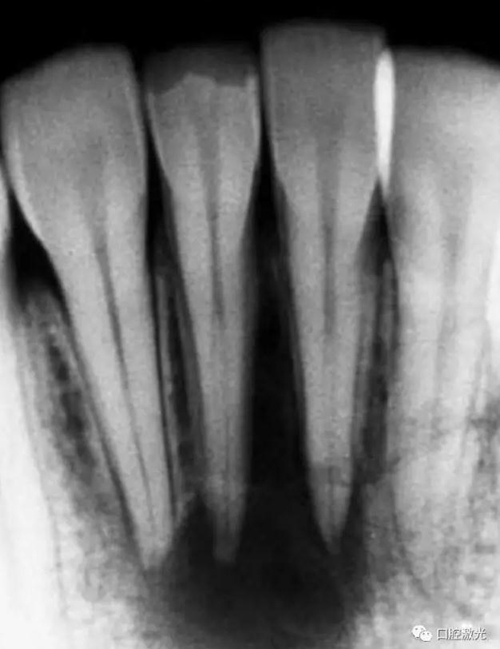

41 治療前X光片